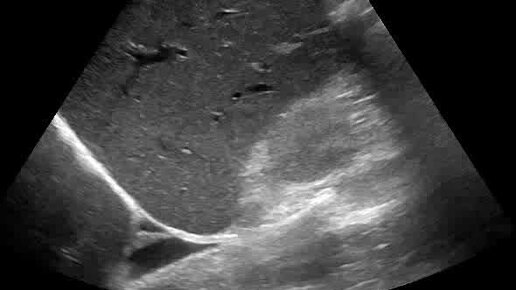

Умеренный правосторонний гидроторакс

Ультразвуковые находки от врача УЗД Зорина Я.П.